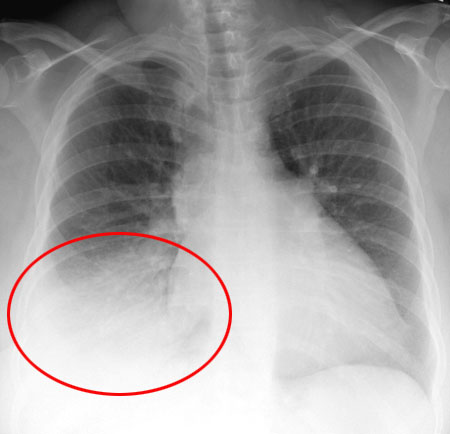

Pleural effusion

A pleural effusion is an abnormal amount of fluid around the lung. Pleural effusions can result from many medical conditions. Most pleural effusions are not serious by themselves, but some require treatment to avoid problems.

Symptoms of Pleural Effusions

Pleural effusions often cause no symptoms. Symptoms are more likely when a pleural effusion is moderate or large-sized, or if inflammation is present. Symptoms of pleural effusions may include:

- Shortness of breath

- Chest pain, especially on breathing in deeply (pleurisy, or pleuritic pain)

- Fever

- Cough